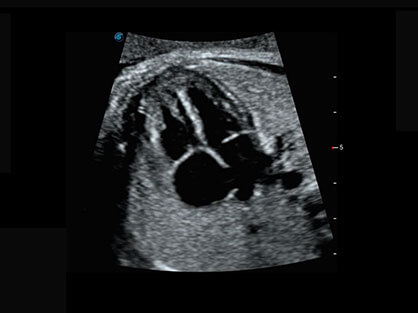

作为P系列家族成员之一,P40 Plus采用开立高端超声系统平台——极光,并以时尚秀丽、小巧灵动的外观设计绽放出灵动之韵、科技之美。高端平台的使用保证了P40 Plus优质的基础图像;完备的高级功能可满足您全身应用的基本需求;丰富的探头配置、多样的高级4D成像及分析软件为您日益增多的妇产应用需求提供丰富的诊疗方案。

结合开立超宽频带探头技术优势,能够更好地获得高分辨力与高穿透力的平衡,保证图像质量,为临床诊断保驾护航。

微米成像技术提升了对组织斑点噪声信号的抑制能力,并进一步强化边界信息,从而获得清晰图像。